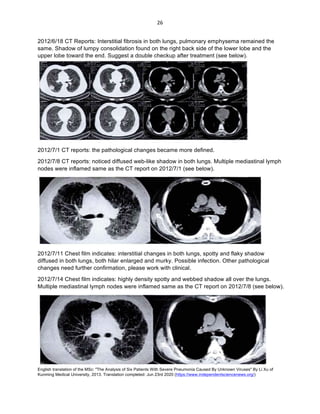

2012/6/18 CT Reports: Interstitial fibrosis in both lungs, pulmonary emphysema remained the

upper lobe toward the end. Suggest a double checkup after treatment (see below).

2012/7/1 CT reports: the pathological changes became more defined.

2012/7/8 CT reports: noticed diffused web-like shadow in both lungs. Multiple mediastinal lymph

nodes were inflamed same as the CT report on 2012/7/1 (see below).

2012/7/11 Chest film indicates: interstitial changes in both lungs, spotty and flaky shadow

changes need further confirmation, please work with clinical.

2012/7/14 Chest film indicates: highly density spotty and webbed shadow all over the lungs.

Multiple mediastinal lymph nodes were inflamed same as the CT report on 2012/7/8 (see below).